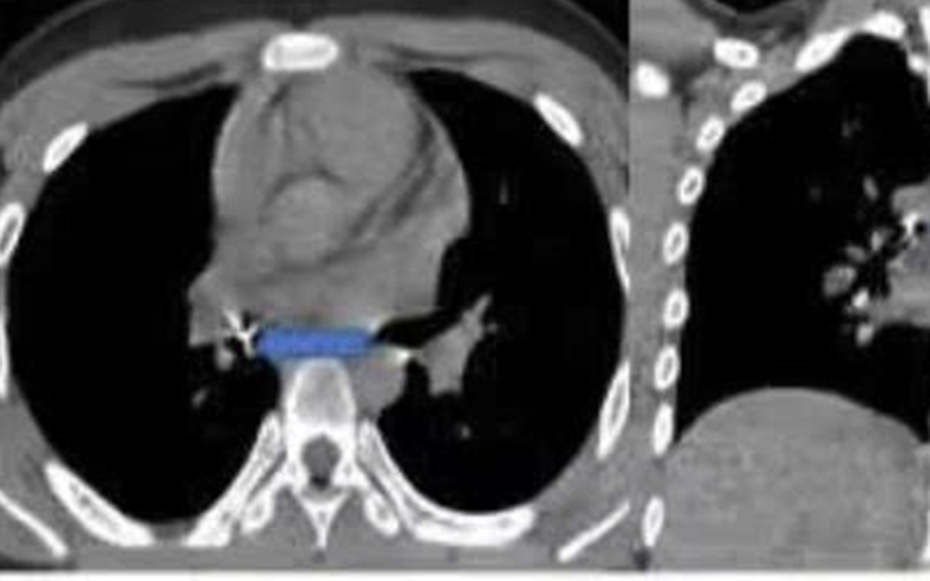

Hình ảnh nội soi ống mềm gắp dị vật đinh ghim xuyên thành phế quản trung gian. Ảnh: BVCC

Sau hơn hai giờ can thiệp tại cơ sở ban đầu không thành công, bệnh nhi được chuyển khẩn cấp tới Bệnh viện Phổi Trung ương. Tiếp nhận ca bệnh, ThS.BSCKII Nguyễn Lê Nhật Minh - Trưởng khoa Nội soi chẩn đoán và can thiệp cùng ê-kíp đã tiến hành nội soi phế quản ống mềm để gắp dị vật.

Theo bác sĩ Minh, dị vật là chiếc đinh ghim sắc nhọn, đầu ghim cắm sâu vào thành phế quản, thao tác lấy rất khó bởi bệnh nhi có phản xạ ho, cần thao tác nhanh, chính xác để tránh làm rách thành phế quản hoặc đẩy dị vật xuống sâu hơn, có thể gây nhiễm trùng, tràn khí màng phổi hoặc suy hô hấp cấp.

Ê-kíp đã cẩn trọng dùng kìm nội soi chuyên dụng gỡ phần đầu ghim khỏi thành phế quản, sau đó từ từ gắp cả dị vật ra ngoài. Toàn bộ thủ thuật diễn ra trong khoảng 15 phút và thành công.